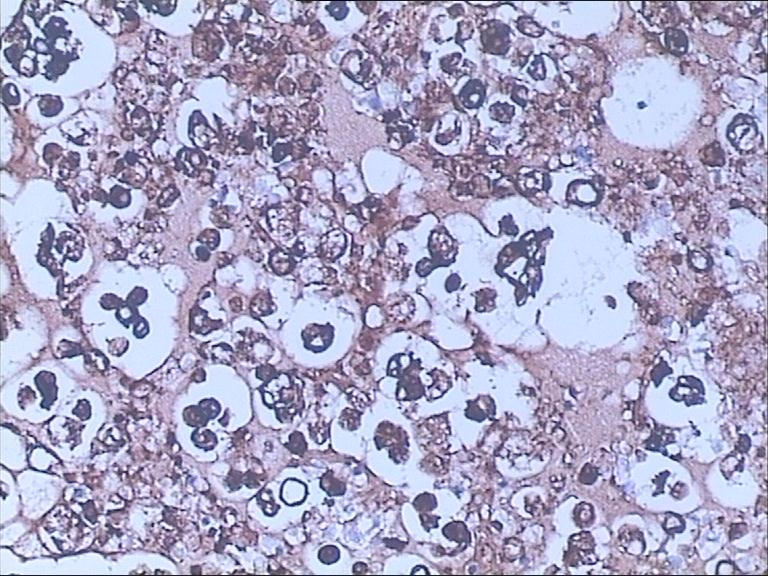

图2为细胞块免疫组化染色

3、细胞蜡块切片细胞多且集中,背景清晰,染色鲜艳,并有一定组织结构,免疫组化染色效果好,阳性定位准确,可靠性高,结合免疫组化结果可明确来源及类型。